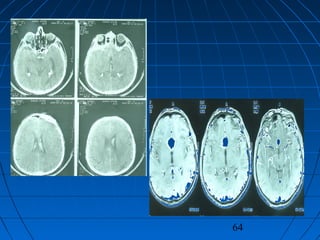

 S.Ç.: 32 yaşında kadın hastaS.Ç.: 32 yaşında kadın hasta

 Ani şiddetli başağrısı, B-KAni şiddetli başağrısı, B-K

CERRAHİCERRAHİ

 Sol frontoparyetal geniş kranyotomiSol frontoparyetal geniş kranyotomi

 AVM’nin total rezeksiyonuAVM’nin total rezeksiyonu